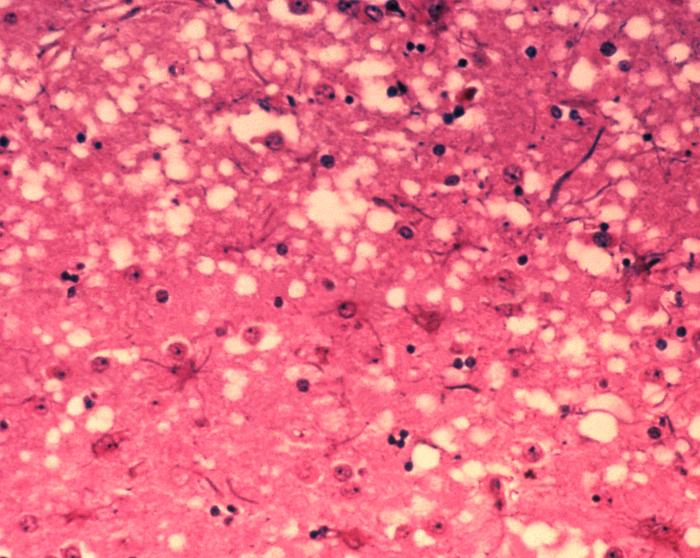

Микроскопичните „дупчици“ са една от ключовите характеристики на тъкани, засегнати от прионите. Източник: Dr Al Jenny/Public Health Image Library, APHIS / Wikimedia Commons